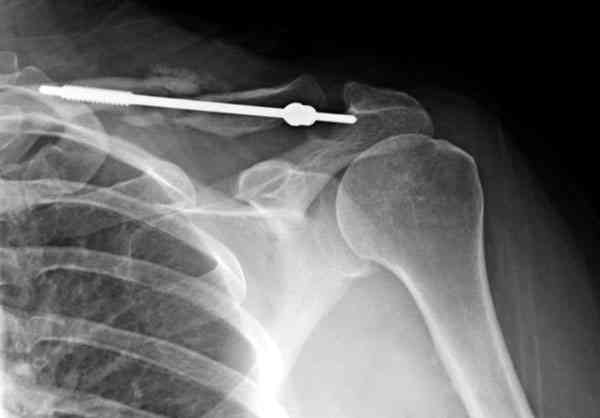

ГГШ> Результат стационарного лечения приведен на рентгенограмме (Xray_3).

Это картинка то есть через неделю после травмы, при выписке? Более чем приемлемо.

после изучения рентгенограмм могу сказать следующее:

1) после репозиции стало хуже

2) стояние фрагментов при выписке идентично таковому при пступлении - с выраженным смещением

Уважаемая Г.В. Полностью согласен с Вашим постом.Закрытая репозиция и кольца Дельбе отлично зарекомендовали себя за 35 лет практики. В обсуждаемом случае представленные Р-граммы сами говорят за себя, 1 снимок (до лечения) и 3 снимок (после лечения) абсолютно идентичны, 2 снимок сделан в несколько иной позиции.Как говорится "комментарии излишни". Согласитесь, что результат лечения мог бы быть и лучшим.